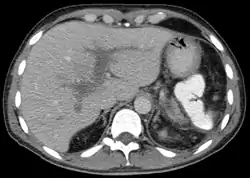

يتم تشخيص خثرة الوريد البابي عن طريق الموجات الفوق صوتية، التصوير المقطعي، أو صور الرنين المغناطيسي